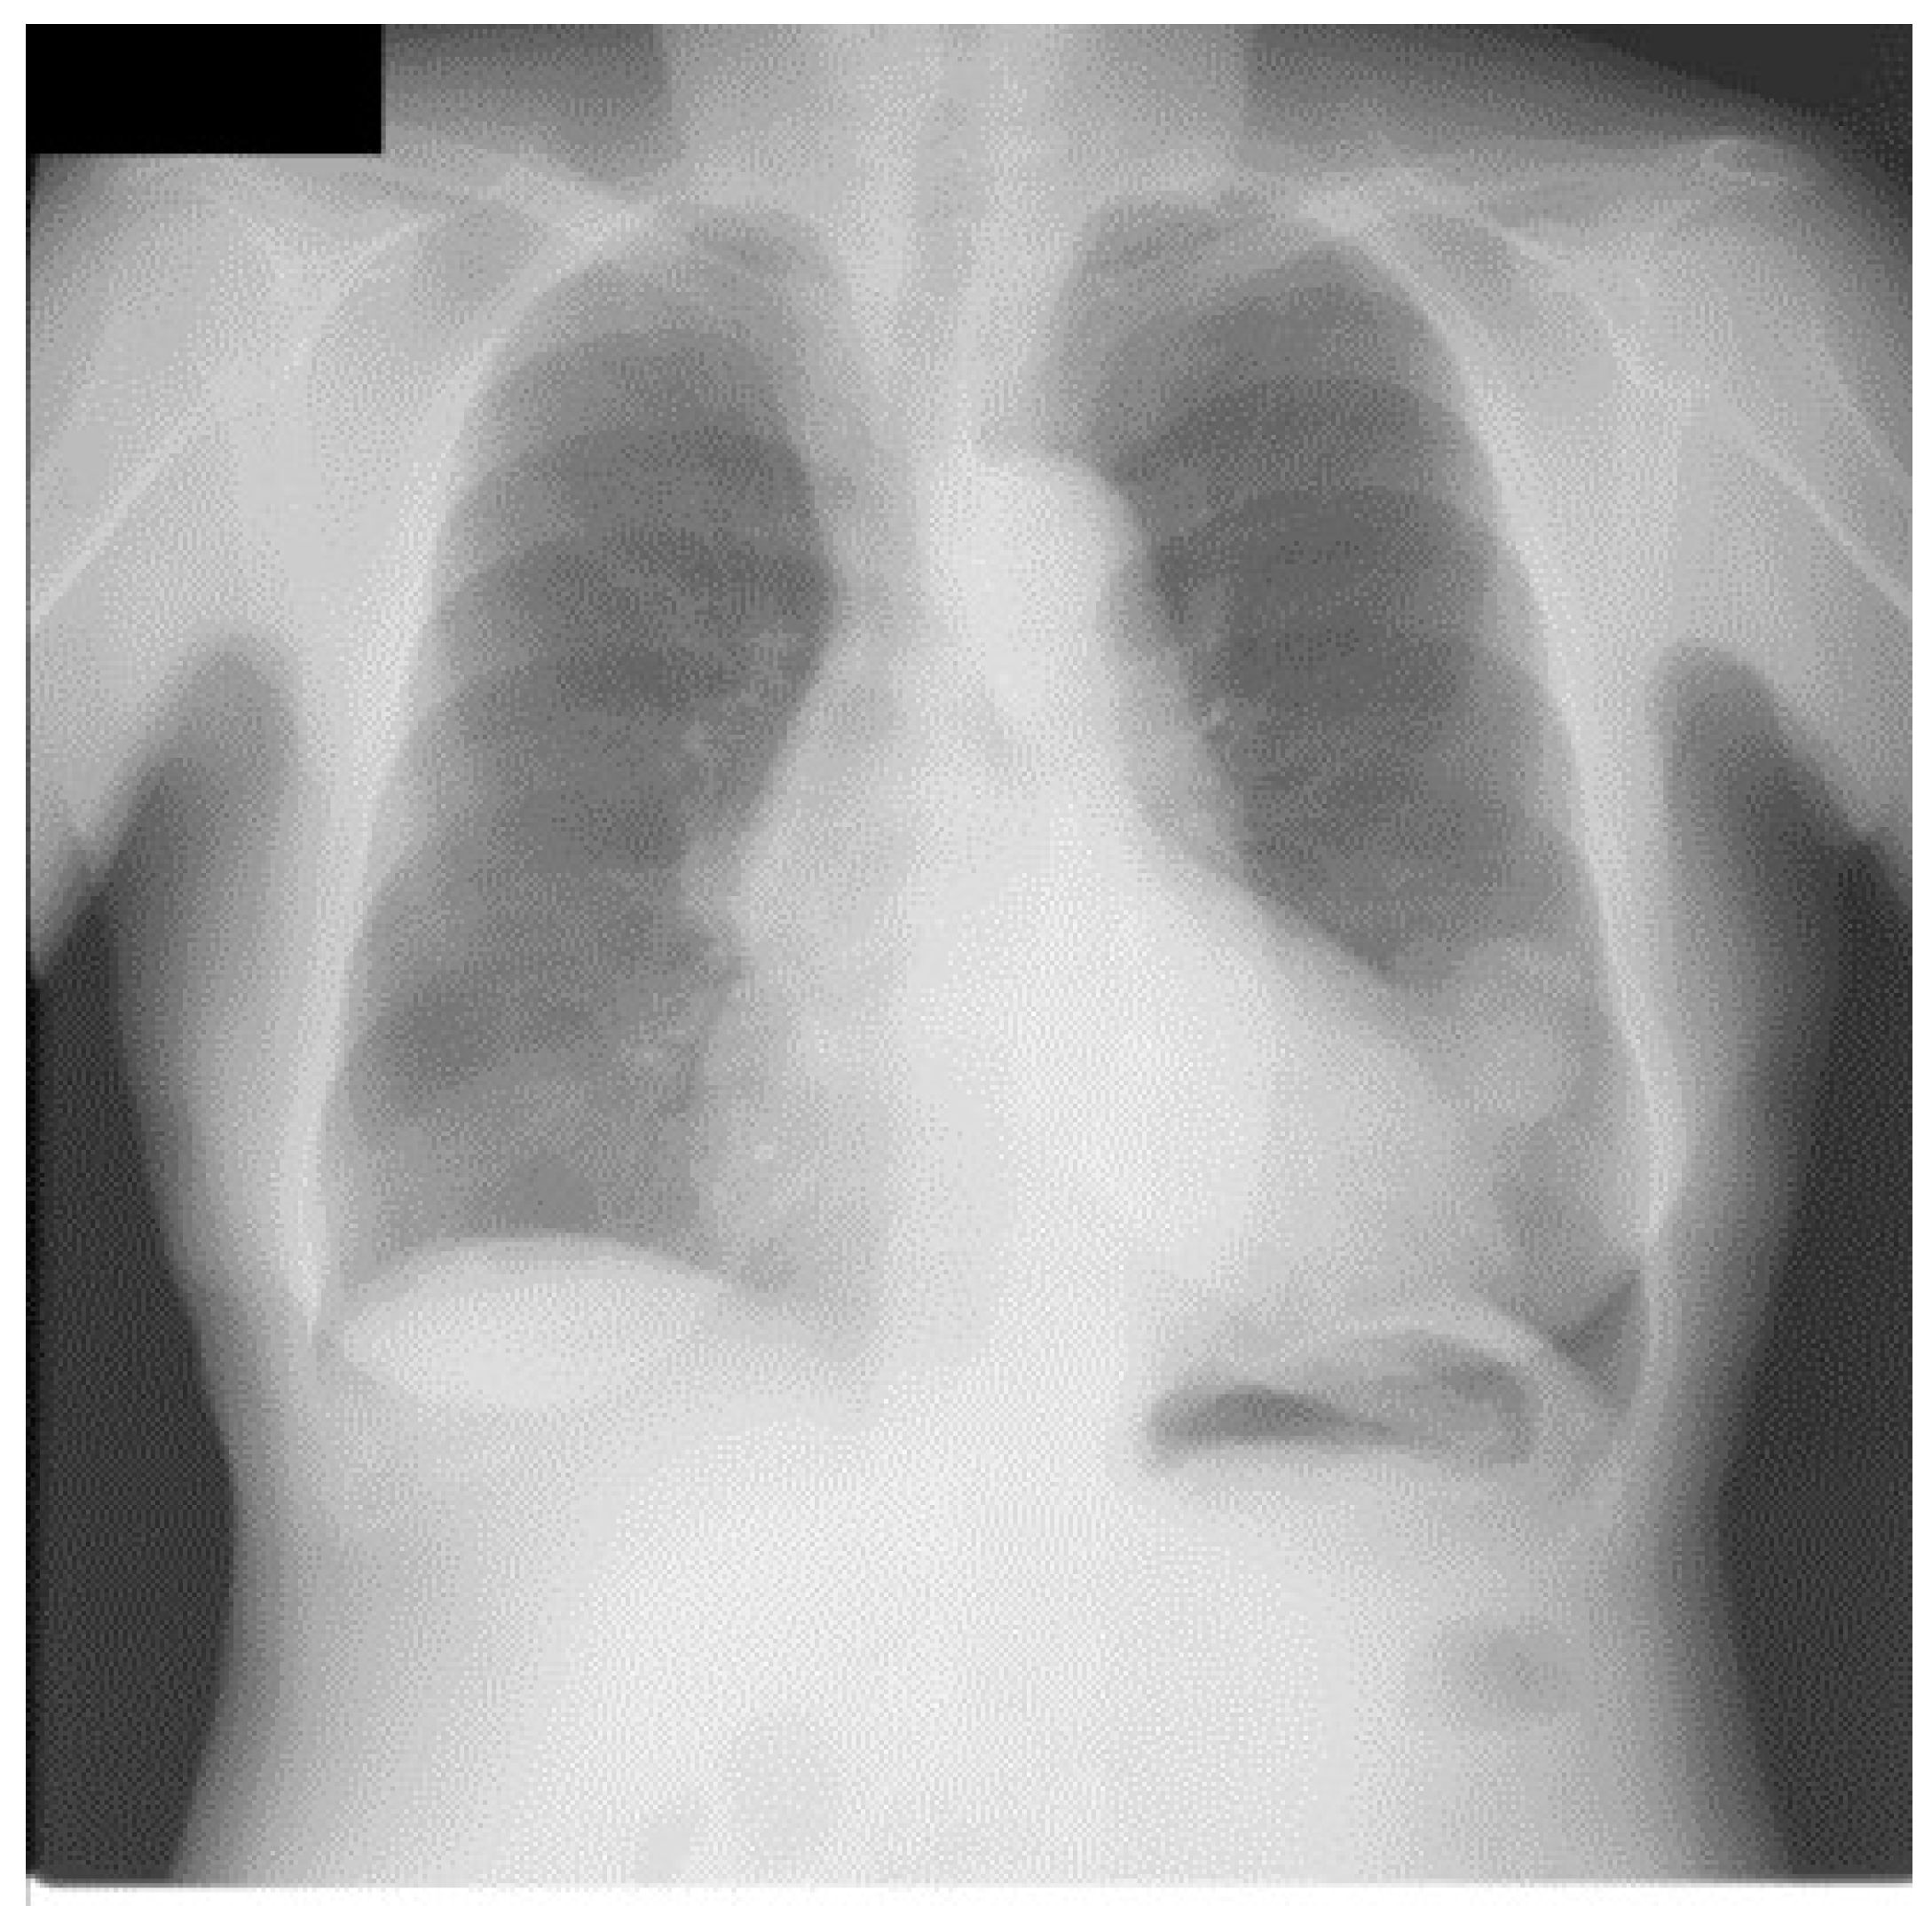

Figure 3.

An image from portable chest radiograph (CXRs) database.